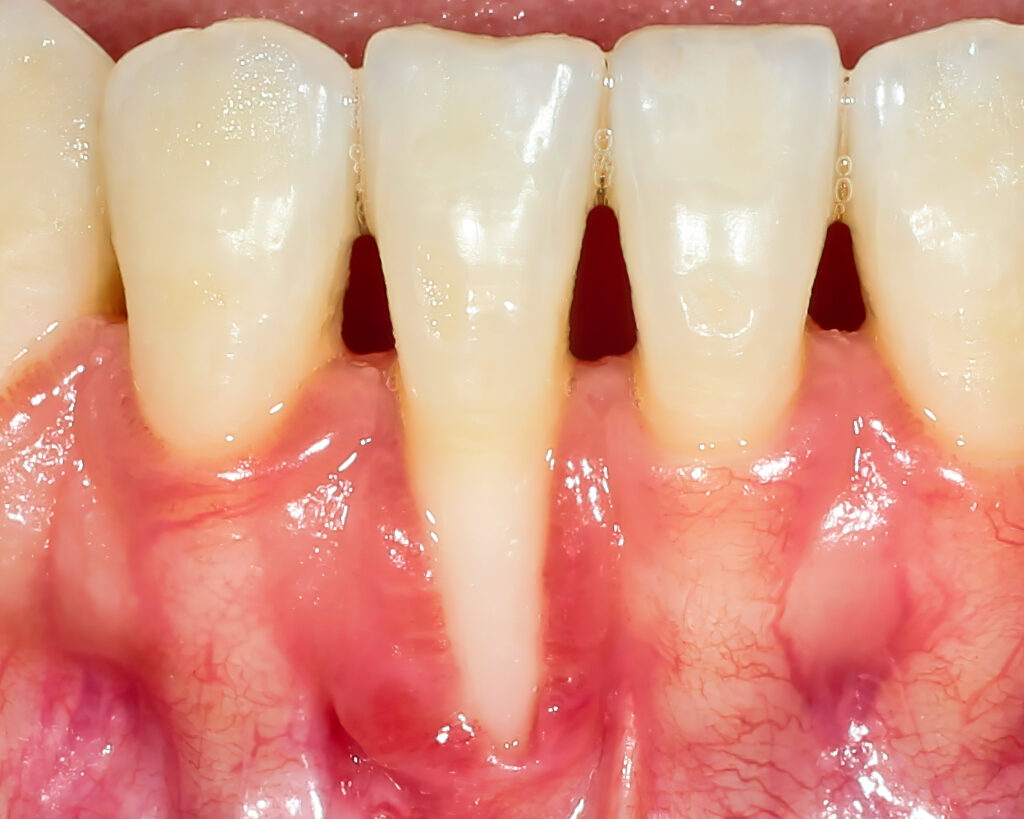

Az ínyrecesszió kezelése a parodontológia egyik leggyakoribb, ugyanakkor legnagyobb kihívást jelentő területe. Amikor az íny visszahúzódik, a fog gyökérfelszíne szabaddá válik, ami nemcsak esztétikai problémát okozhat, hanem érzékenységgel, gyulladásos kockázattal és hosszú távon további szövetvesztéssel is együtt járhat.

A keresztkötött xenogén kollagén mátrix (VCMX) több szempontból is előnyös megoldást jelent az ínyrecesszió kezelésében. Alkalmazásához nincs szükség szövetvételre egy másik területről, térfogatát hosszú távon megőrzi, és azonnal felhasználható. Emellett biológiai vázként szolgál, amely elősegíti a lágyszövetek gyógyulását és természetes érését.